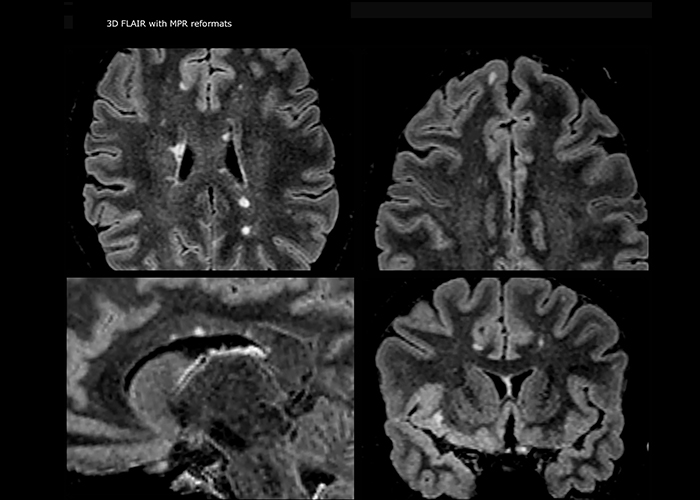

Wenn ein Verdacht auf multiple Sklerose (MS) besteht, muss das Klinikteam schnell zu einer Diagnose kommen, damit die Behandlung so bald wie möglich beginnen kann. „Eine Schwierigkeit bei der Bildgebung ist, dass MS-Läsionen im Gehirn und in der Wirbelsäule sehr klein sein können“, erläutert Dr. Savatovsky. „Wir benötigen eine präzise Bildgebung, um exakt zu bestimmen, wo sich die Läsion befindet, das heißt, wir brauchen hochwertige Bilder in sehr hoher Auflösung, vorzugsweise in 3D[1]. Wir müssen uns sicher sein, ob eine hohe T2-Signalintensität auf MS hinweist oder lediglich aspezifisch ist. Außerdem wünschen wir uns eine sehr gute Visualisierung von aktiven Läsionen.“

„Ingenia 3.0T liefert uns eine sehr gute Bildqualität mit hohem Signal-Rausch-Verhältnis, auch wenn wir die Auflösung ausreizen. Bei FLAIR-Bildern haben wir zum Beispiel eine isotrope Auflösung von 0,9 mm. Ingenia ermöglicht uns die Nutzung von 3D-T1-TSE mit BrainView, was eine bessere Empfindlichkeit als die 2D-Spinecho-Bildgebung[2] und die 3D-Gradientenecho-Bildgebung aufweist. Ingenia liefert auch hoch reproduzierbare Untersuchungen, was bei der MS-Bildgebung wichtig ist, damit Folgeuntersuchungen zu verschiedenen Zeitpunkten auf dieselbe Weise durchgeführt werden.“

Für die MS-Bildgebung im Gehirn nutzt Dr. Savatovsky 3D-FLAIR als Basissequenz, um die Läsionen darzustellen sowie die jeweilige Situation und die Läsionsbelastung zu beurteilen. „Wir zählen die Läsionen an jeder Stelle, um zu bestimmen, ob die Kriterien der Erkrankung erfüllt sind. Dafür wird eine T2-gewichtete Sequenz verwendet, weil unsere Neurologen diese gewohnt sind. Wir vergleichen die Läsionsbelastung unter FLAIR mit einer 3D-T1-Postkontrastsequenz, damit wir feststellen können, ob die Läsionen alt oder neu sind. In der Regel verabreichen wir das Kontrastmittel vor der Aufnahme des Patienten in das System, weil sich dadurch die Untersuchungsdauer verkürzt und die Visualisierung aktiver Läsionen möglich wird, die im Allgemeinen nach mehreren Minuten deutlicher dargestellt werden. Wenn sich eine differenzielle Diagnose als schwierig herausstellt, nutzen wir weitere Sequenzen wie die Suszeptibilitätsbildgebung, da einige fokale MS-Läsionen in der Mitte eine kleine Ader aufweisen[3].“